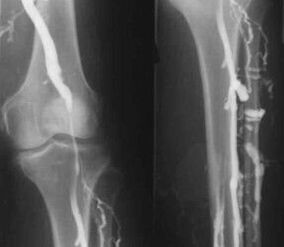

O método de diagnóstico instrumental máis común é o uso do exame de ultrasóns dos vasos venosos das pernas. Esta técnica permítelle visualizar o sistema vascular e identificar o grao de progreso do proceso patolóxico.

- Flebografía.

- Fotopletismografía.

O uso da pletismografía de oclusión venosa permite determinar o volume de sangue nas veas das extremidades inferiores.